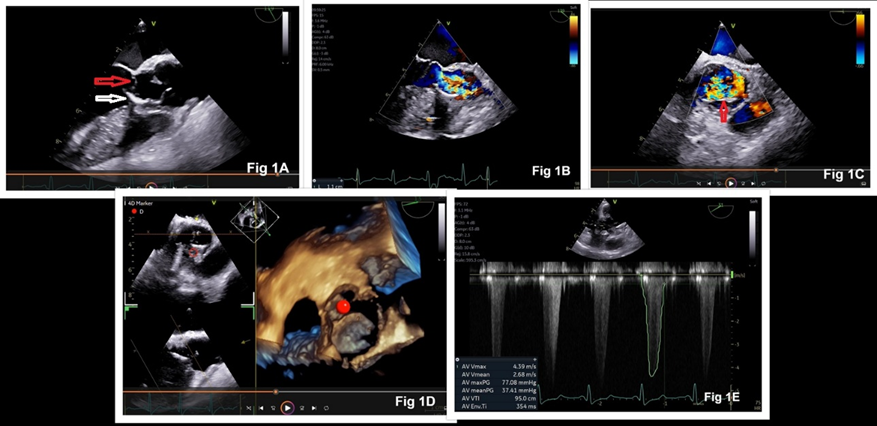

The surgical plan was the extrusion of the VSD occluder device and closure of the VSD using cardiopulmonary bypass (CPB). Informed consent was obtained. Under standard cardiac monitoring, general anesthesia was induced and a transesophageal echocardiography (TEE) probe (6 VT-D transducer, Vivid E95 GE) was inserted. Intraoperative TEE confirmed the preoperative echocardiographic findings and showed significant narrowing of the LVOT (Figure 1A-1D). LVOT gradient measured during intraoperative TEE was 77/37 mmHg (Figure 1E). The surgical procedure consisted of a midline sternotomy, systemic heparinization, bicaval and aortic cannulation, and institution of CPB. During surgery, the VSD occluder device was found to be tightly adherent to the LVOT and the interventricular septum. A forceful extrusion of the device could have led to damage to the aortic valve, the LVOT, the interventricular septum, and other neighboring structures. It could even have led to the formation of an iatrogenic VSD. Therefore, the surgeons decided to remove the left disk of the VSD occluder device by performing its debulking with Rongeur forceps and reassess the relief of LVOT obstruction. The subaortic membrane was resected. After coming off CPB, TEE showed LVOT pressure gradients of 8/4 mmHg (peak/mean), trace aortic regurgitation, a VSD device in situ, and no residual VSD shunt (Figure 2A-2D). The remaining surgical procedure and the postoperative course were unremarkable.

Figure 1: Intraoperative transesophageal echocardiographic images showing occluder device obstructing the left ventricular outflow tract {LVOT} (white arrow), subaortic membrane (red arrow, Figure 1A), narrow LVOT (1.1 cm, Figure 1B), turbulent blood flow in aortic valve (Figure 1C), occluder device in LVOT in 3D view (Figure 1D), and pressure gradient across LVOT (Figure 1E)